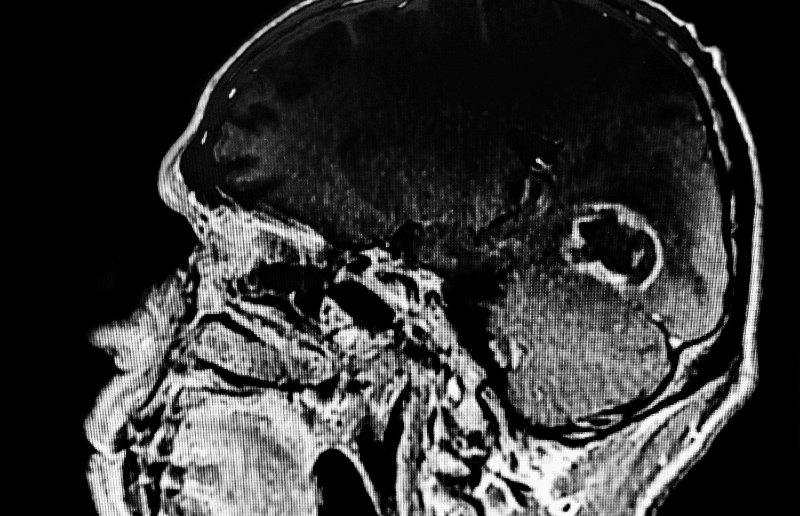

Beynimizdeki sessiz işgalci